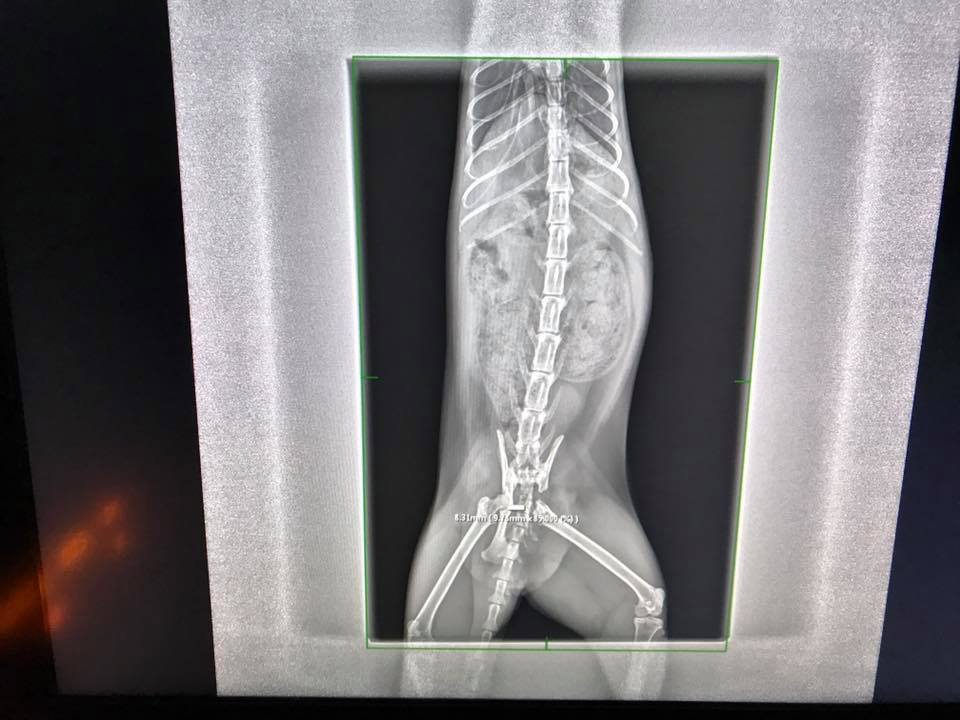

今日回診,因為他出來的大便都是扁的(狹窄還是很嚴重 灌腸時 手指還是被壓住的狀態),X光看附近有長出骨片,但不清楚是否會影響,建議照一下斷層掃描 並且再帶去給亞太看,而且肚子裡的大便也沒有那麼硬,不過腸子確實也變寬了,目前先取消楊車前子粉,讓肚子的便便先趕快排出